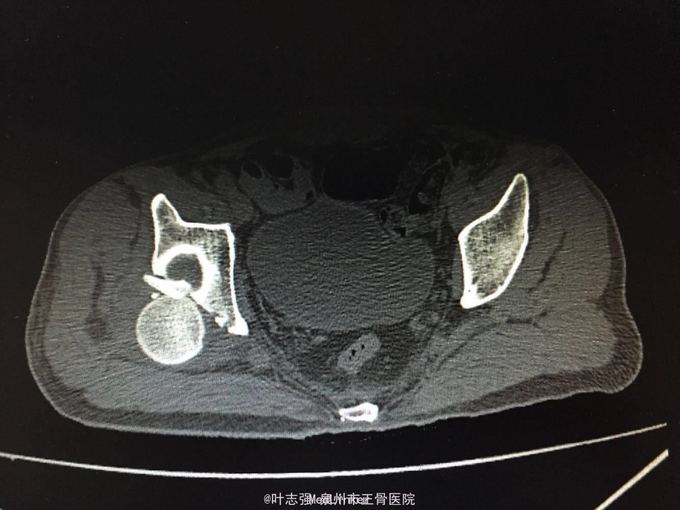

髋臼骨折伴髋关节后脱位ORIF

车祸致左髋部疼痛、活动受限1天。 53岁男性

左髋臼骨折伴髋关节后脱位 行生命支持,股骨髁上骨牵引,